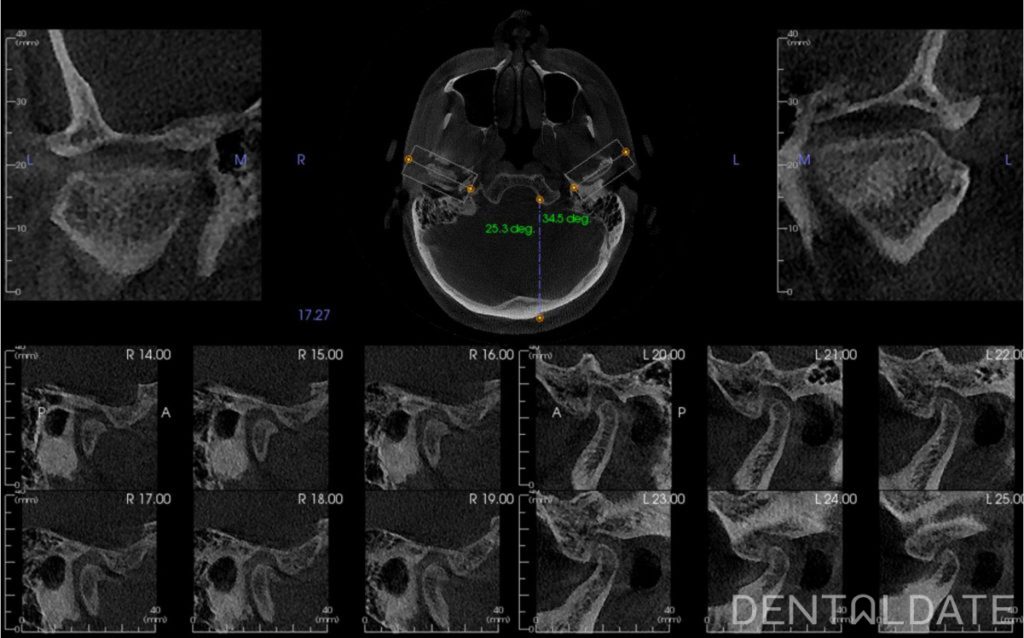

To correct the position of the lower jaw, we used a custom-made splint designed based on condylography results. Just five days after starting therapy, the patient reported complete relief from all previous symptoms, including significant posture improvement and reduced muscle tension.